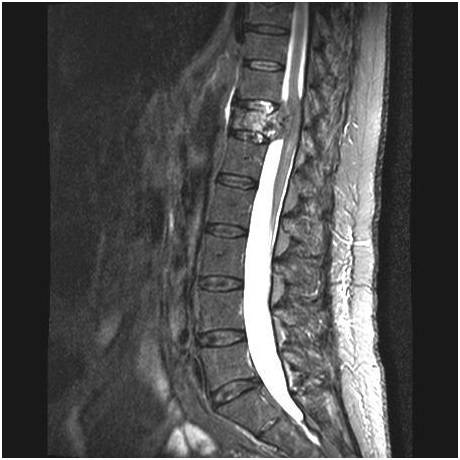

Диагностировать опухолевые образования в позвонках лучше всего с помощью КТ позвоночника или МРТ позвоночника с контрастом.

| МРТ опухоль позвоночника | МРТ опухоль спинного мозга | МРТ киста спинного мозга |